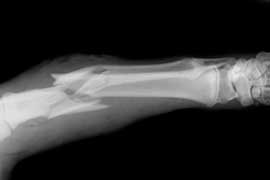

El uso prolongado de bifosfonatos reduce la resistencia a las fracturas

Luego de un uso promedio de 8 años, los bifosfonatos mostraban tejido cortical más mineralizado pero con menor resistencia al inicio y progresión de la fractura femoral. PNAS, 31 de julio de 2017